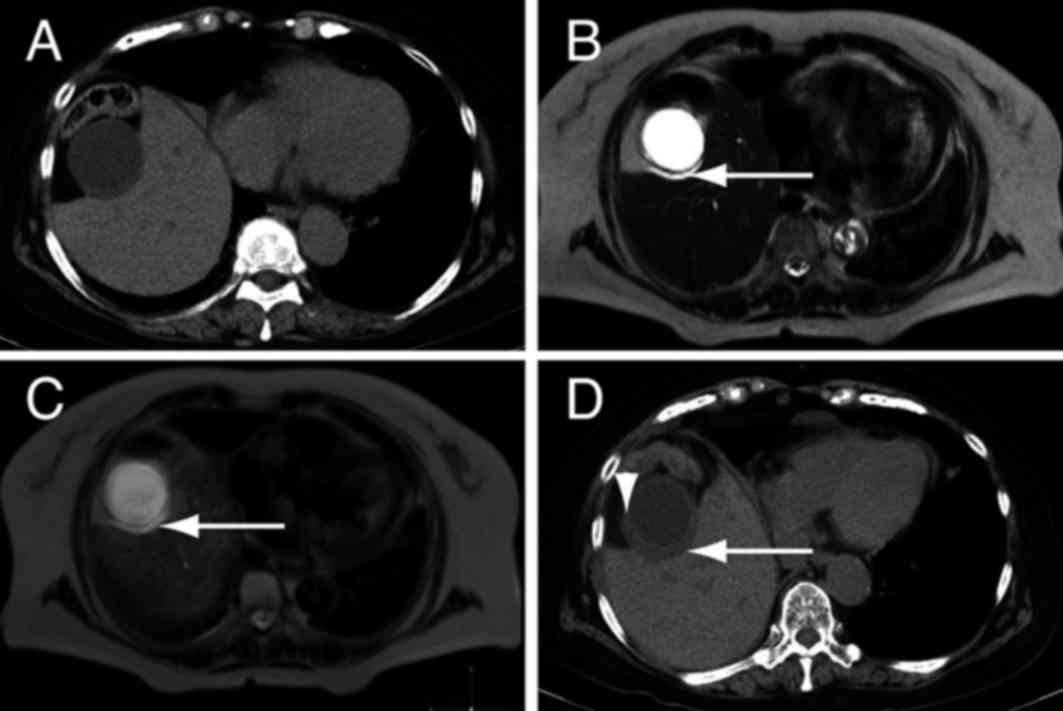

The sensitivity of DWIBS/T2 in the diagnosis of acute cholecystitis was determined. Images obtained by DWIBS/T2 from patients with acute cholecystitis (n=11) were evaluated to determine the extent of wall thickening and signal intensity, both positive indicators of cholecystitis. Out of the 11 patients, 10 exhibited a thickened wall and high signal intensity in the DWIBS/T2 images (Table II). Thus, positive DWIBS/T2 results were obtained in 10/11 patients (90.9%). In the remaining patient, fluid was present between the liver and gallbladder, indicating acute cholecystitis (Fig. 2A and B). The patient's DWIBS/T2 result was positive for cholecystitis (Fig. 2C), and a CT scan performed three days later identified thickening of the gallbladder wall (Fig. 2D). Disparity between results of the DWIBS/T2 and CT scans may be due to a lack of high signal intensity in DWIBS/T2 in the absence of wall thickening. Alternatively, DWIBS/T2 may infrequently yield a negative result for acute cholecystitis. Nevertheless, these results suggest that high signal intensity detected by DWIBS/T2 is associated with the severity of gallbladder inflammation in acute cholecystitis.